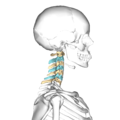

في الفقاريات، الفقرات العنقية Cervical vertebrae، (مفردها فقرة عنقية vertebra)، هي الفقرات التي تقع أسفل الجمجمة مباشرة.

وتتكون من سبع فقرات مرقمة تسلسلياً منلأعلى إلى أسفل. تسمى الفقرة الأولى بالفهقة وهي تشبه الحلقة، وتكون مع قاعدة الجمجمة من أعلى بالمفصل الفهقي. وتسمى الفقرة العنقية الثانية بالمحور حيث يخرج منها بروز إلى أعلى كأنه وتد أو محور. ويربط هاتين الفقرتين مفصل يسمى المفصل المحور الفهقي حيث يدخل الوتد في الجزء الأمامي من حلقة الفهق ويمتد رباط من جانبي الحلقة من الداخل ليحافظ على استقرار المفصل.